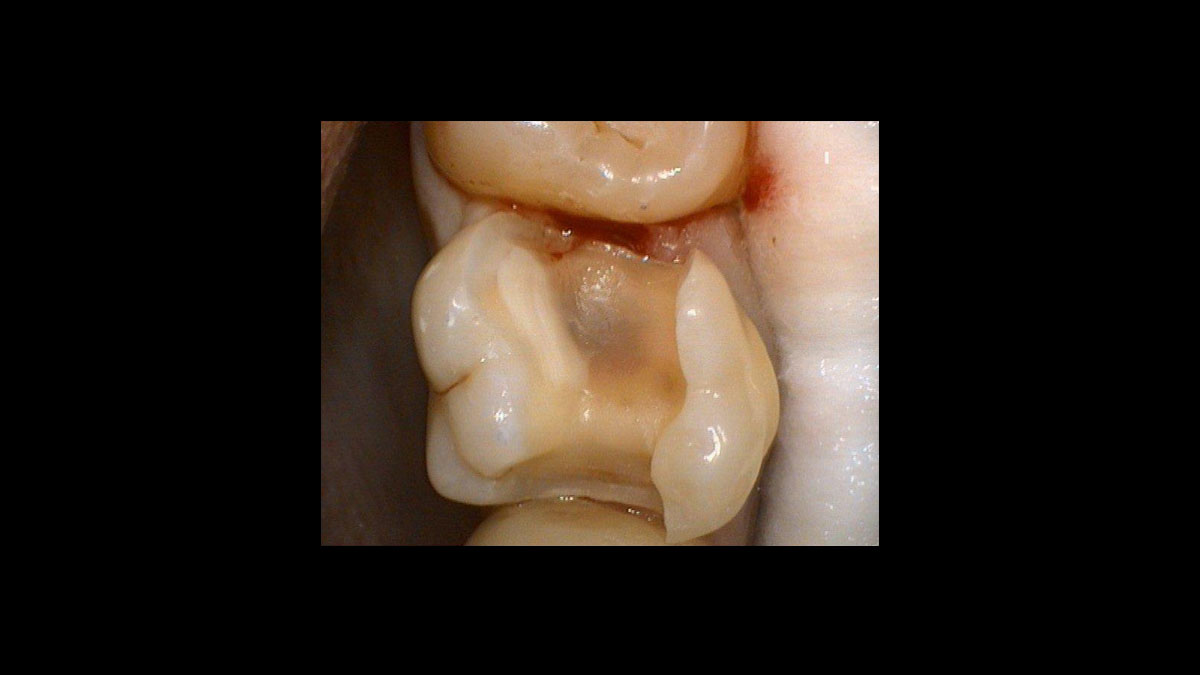

Operculectomy